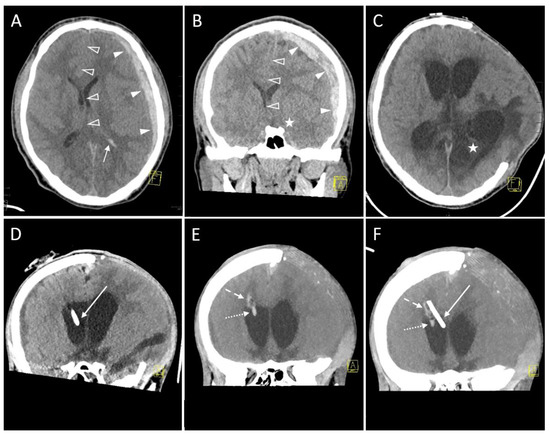

3.2.4. Hemorrhage

| Trauma | 7 (24.1) 2 |

| Hemorrhage on follow-up CT | |

| No evidence of hemorrhage | 32 (88.9) * |

| Grade 1 (<1 mL) | 3 (8.3) * |

| Grade 2 (≥1 to 15 mL) | 1 (2.8) * |

| Grade 3 (>15 mL) | 0 (0.0) * |